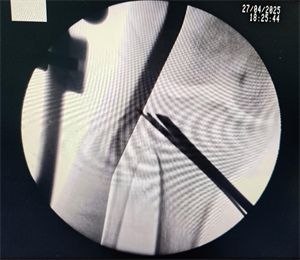

手术团队通过 X 线、CT 等影像学评估,精确计算出下肢力线偏移角度,确定截骨位置及矫正目标;术中采用开放楔形截骨术(OWHTO),在胫骨近端内侧作小切口,借助导向器完成截骨后,撑开骨间隙植入人工骨材料,并用解剖钢板固定,整个过程出血量不足 50ml,耗时约 1 小时,术后患者下肢力线即刻恢复生理曲度;术后第三天,患者便开始部分负重行走,摄片检查显示下肢力线已纠正,结合股四头肌锻炼、关节活动度训练等个性化康复训练,4 周后逐步过渡至完全负重,膝关节疼痛显著缓解,功能恢复良好。

术中透视下进行截骨